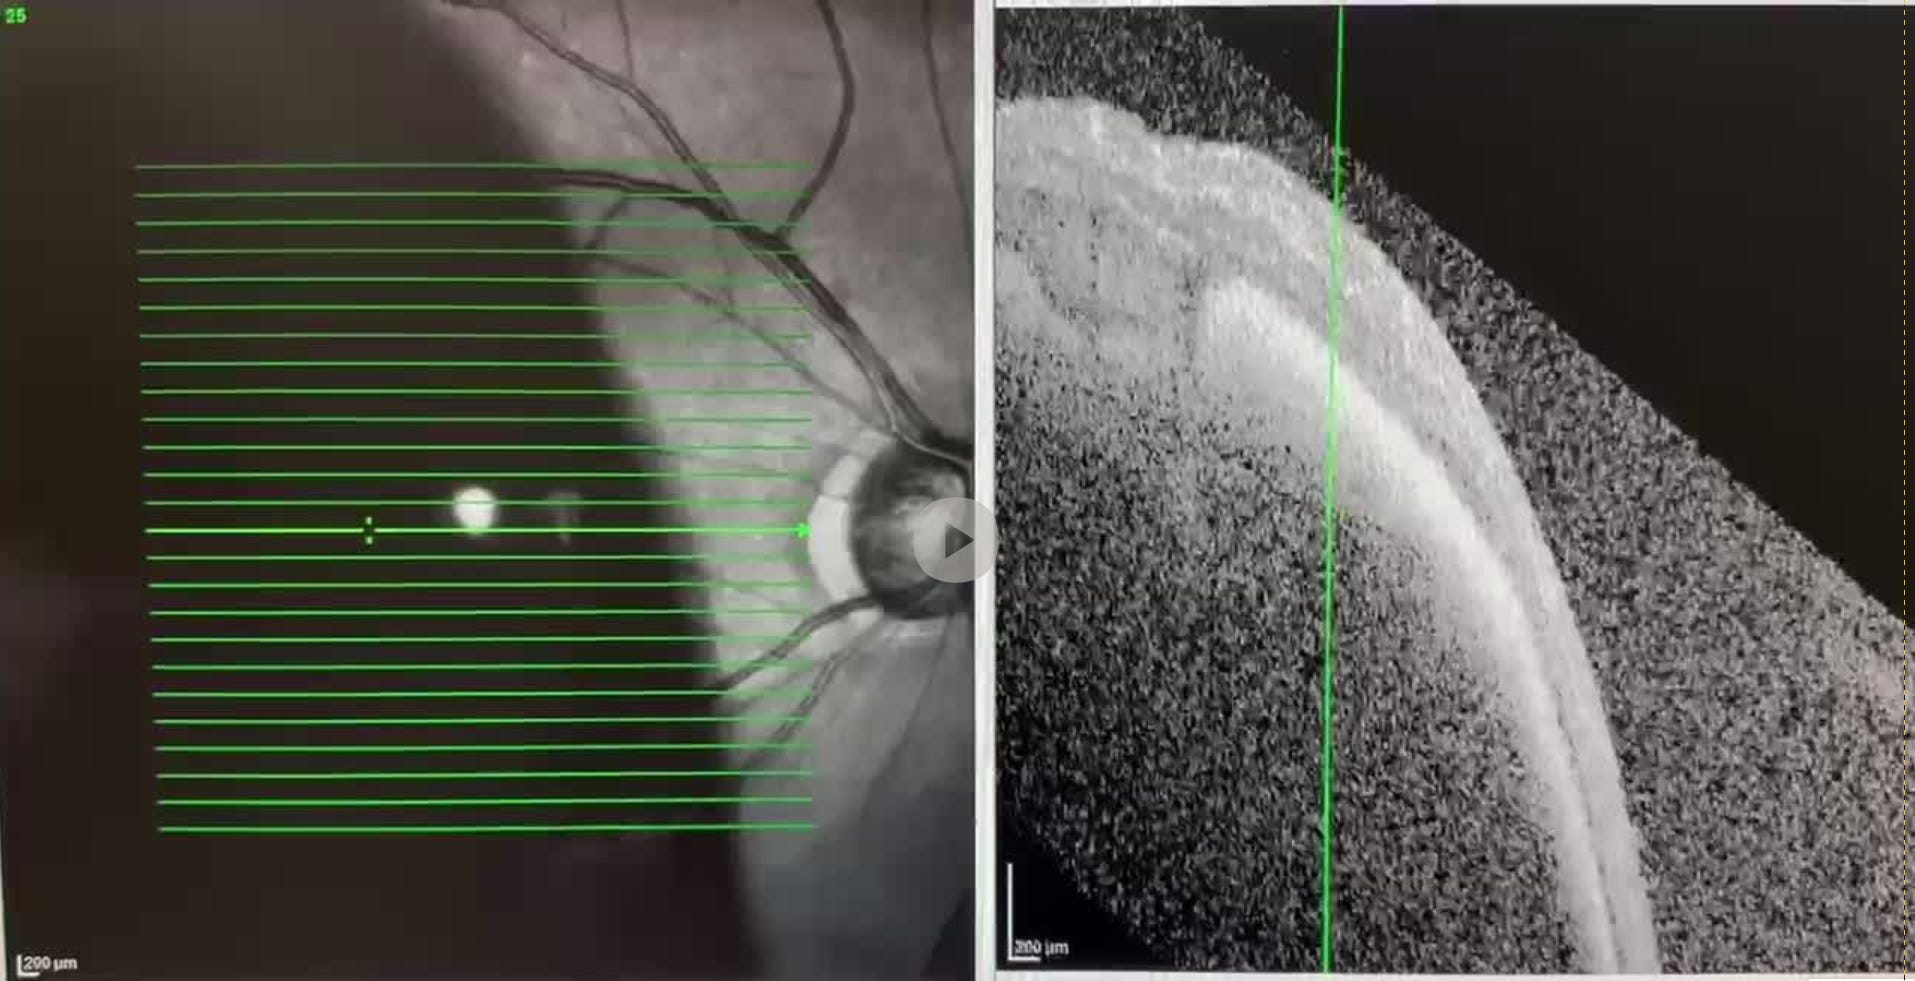

Here are my scans.

I have a lot of blood under my RPE... that is the problem

I have a subretinal hemorrhage (SRH). The good news is I have <500 microns of blood under my retina. That can be cleared with surgery. The BAD news is I have lots of blood under my RPE that cannot.

The big problem is that there is a substantial amount of clotted blood under the very thin RPE layer. If this blood isn’t cleared within about 1 week from now, my RPE will die and so will my vision. Forever.